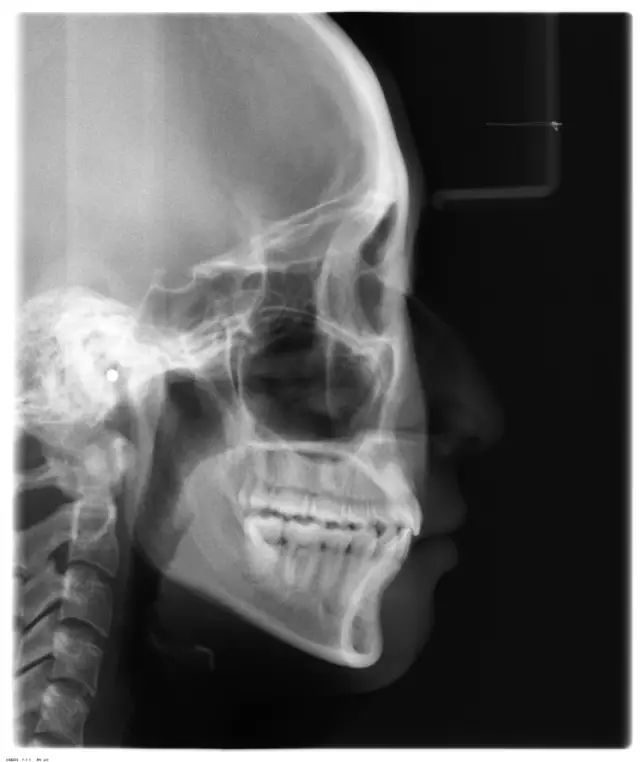

Damon 病例分享:安氏 II 類(lèi)二分類(lèi)露齦笑的矯治(董一磊)

患者信息

治療前后對(duì)比